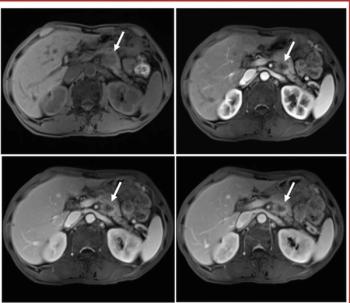

The M-PRiSM risk stratification, which incorporates MRI features, offers a significantly higher C-index, one-year AUC and two-year AUC than the 8th AJCC staging system for predicting postoperative survival for patients with pancreatic ductal adenocarcinoma.